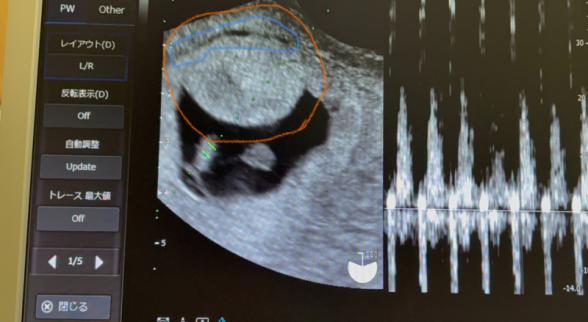

妊娠6w3dの妊婦です。ネットで見る皆さんのエコーに映る胎嚢はまん丸や楕円といった綺麗な形をしていますが私の胎嚢は三日月?のような端っこが尖っており初めて見る形で気になってます。

また胎嚢の上の方に少し血が溜まっているようで自然に吸収されていくことがほとんどなので今は特に気にしないで大丈夫。これが大きくなっていったら絨毛膜下血腫といって流産したりもすると言われてとっても不安です。

先生が仰っている血の部分はこの青で囲んだ部分ですか?それともオレンジで囲んだ部分のことでしょうか?オレンジの部分は確かに丸く腫れているように見える気もします。

ちなみに産婦人科では6週3日時点で卵黄嚢と胎芽、心拍の確認ができ心臓も元気に動いてるので母子手帳を貰いに行ってねと言われ形については何も触れられませんでした。

胎嚢の形については、経膣エコーの機械の当て方によって、みている方向が変わるので形が変わってくるかと思います。

血腫については、血液は黒くうつるので、左下の白い線と子宮の内側の間にあるのかなと思います。